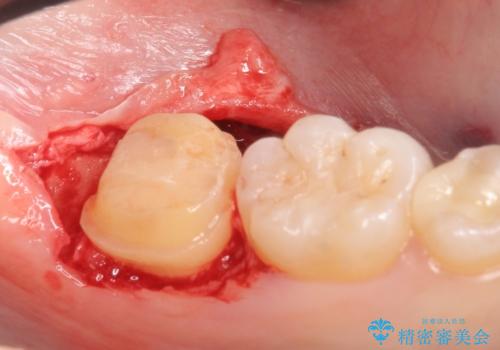

左下7遠心(下記のX線写真の左側)の歯質が歯肉縁下でかつポケットも深かったため、歯茎を下げる歯周外科を行いました。

虫歯が進み歯茎より深くなってしまうと、虫歯を取り残してしまうリスク、樹脂の硬化の妨げ、補綴物の不適合、歯肉炎・歯周病のリスクの増大等様々な弊害が起こり得ます。

そのため当院では歯周外科手術(歯茎を下げる手術)や歯の挺出による、虫歯が歯茎より深いという問題の解決を推奨しております。